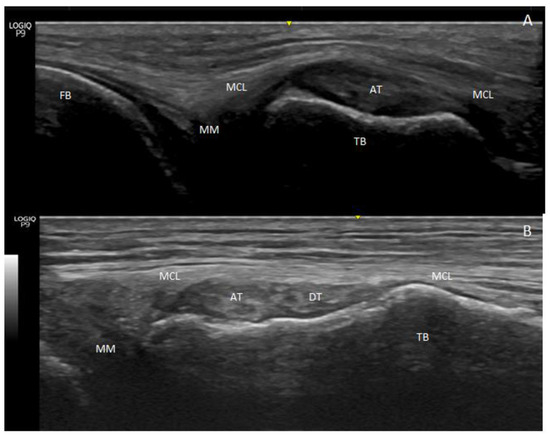

3.1. Ultrasound Study

3.2. Anatomical Study